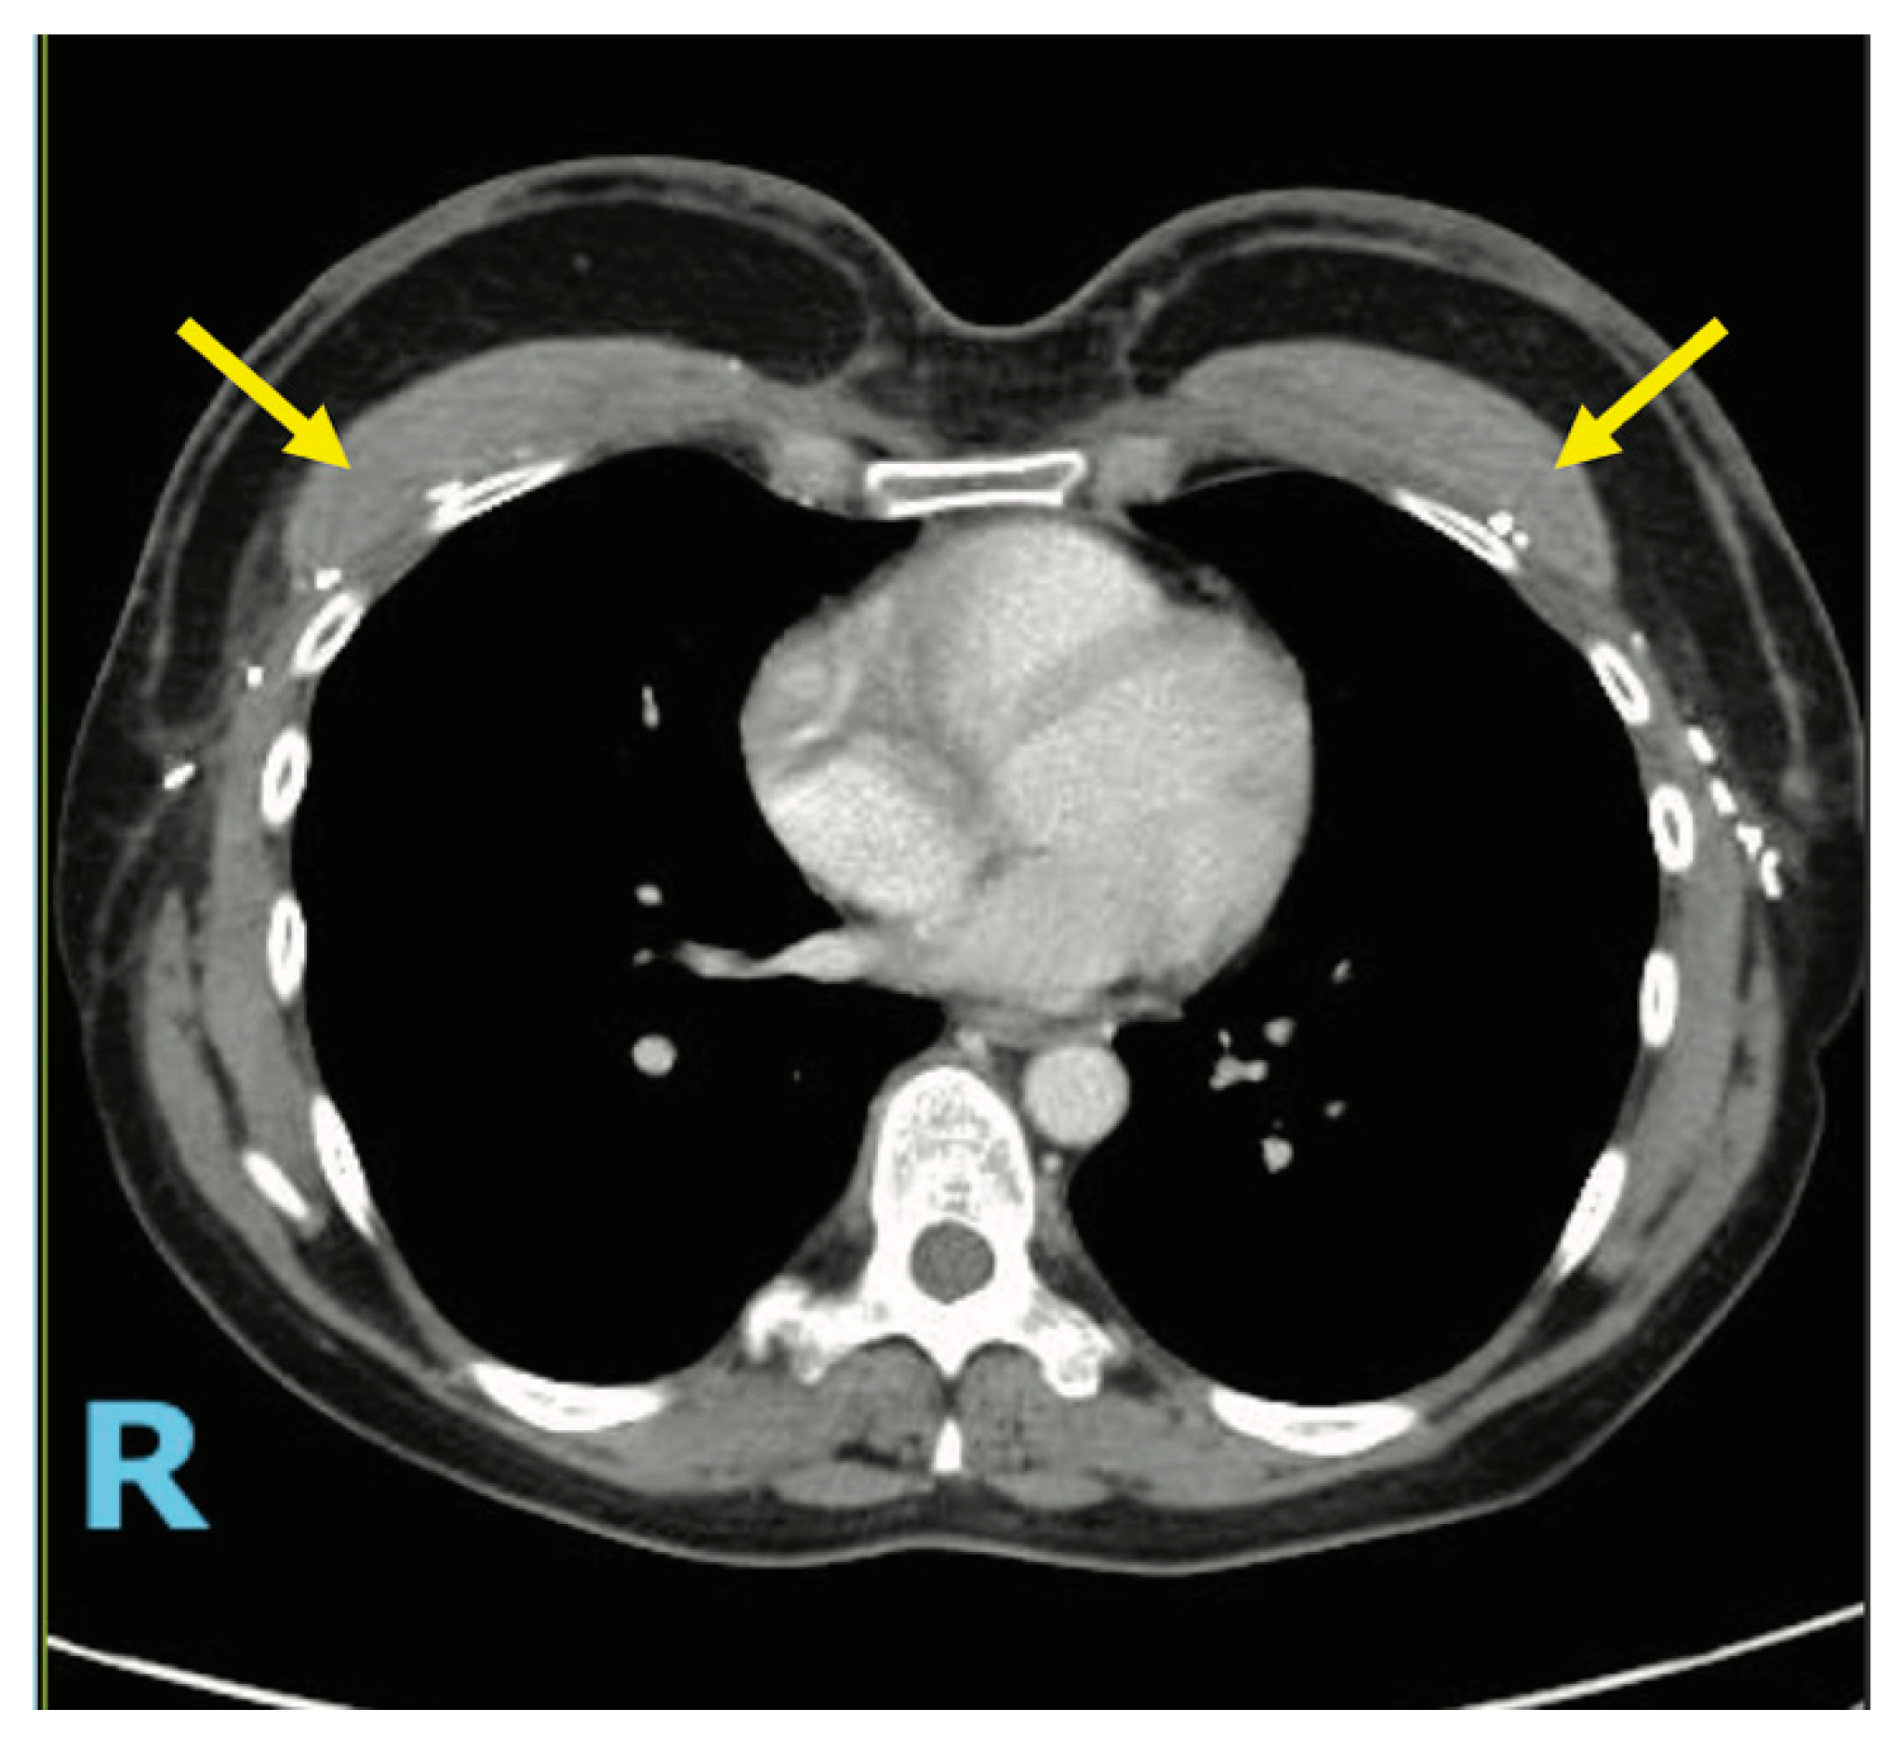

4.3. Case 2—HyPAD®

4.4. Operative Technique